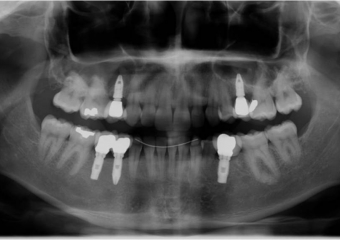

Raio x inicial, com agenesia de dentes permanentes

Raio após implantes instalados